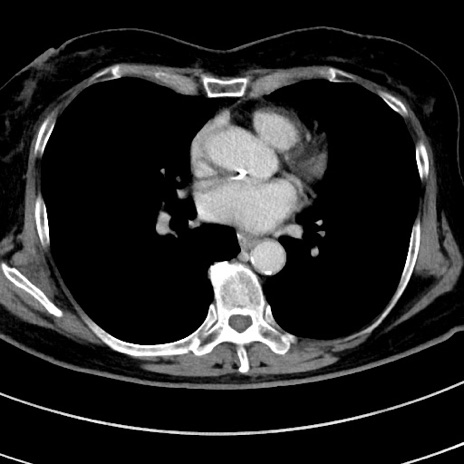

症例9(横断像)

【症例】 60歳代女性

【主訴】むかつき、みぞおちの痛み

【現病歴】3日前よりむかつきがあり、食事がとれない。

【既往歴】糖尿病

【身体所見】発熱なし、心窩部圧痛軽度あるも、腹膜刺激症状なし。

【データ】WBC 7400、CRP 1.92